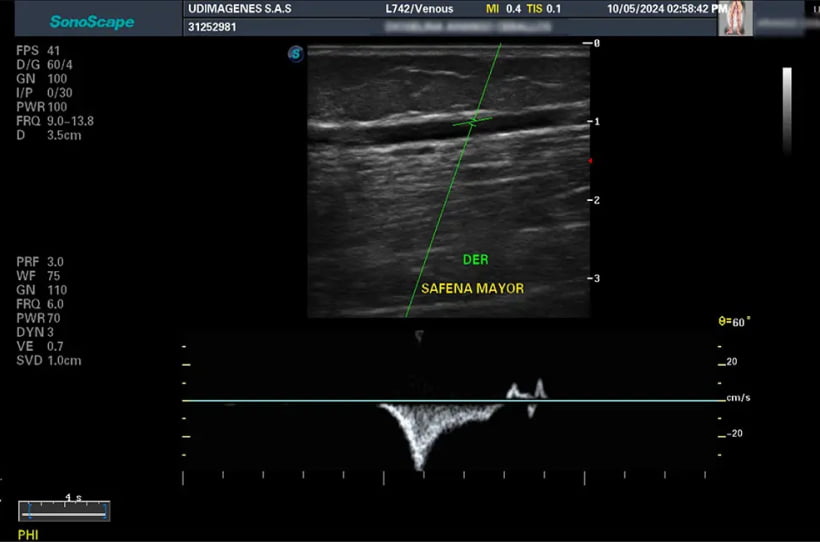

Ecografía Doppler Color

La ecografía Doppler es una técnica avanzada que evalúa el flujo sanguíneo en venas y arterias, crucial para detectar problemas circulatorios. El Doppler venoso se enfoca en las venas para identificar coágulos y varices, mientras que el Doppler arterial examina las arterias para detectar bloqueos y estrechamientos. Nuestro especialista ofrece atención personalizada, asegurando diagnósticos precisos y un cuidado excepcional para cada paciente.

• Doppler de vasos venosos de miembros superiores e inferiores

• Doppler de vasos arteriales de miembros superiores e inferiores

• Doppler de vasos del cuello